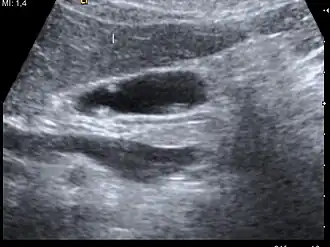

A polyp in the gall bladder as seen on ultrasound

Diagnosis is typically by ultrasound or CT imaging.